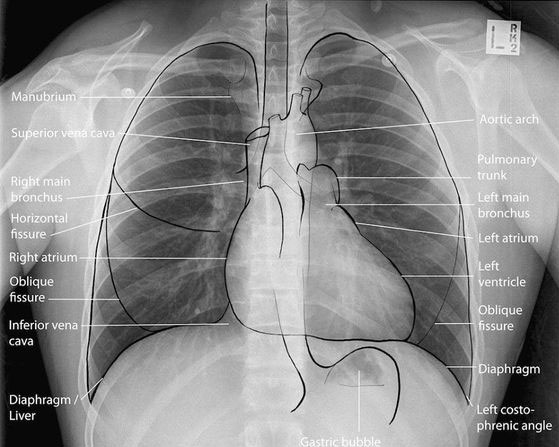

An x-ray (radiograph) is a quick, painless medical test that helps physicians diagnose and treat medical conditions. Radiography involves exposing a part of the body to a small dose of ionizing radiation to produce pictures of the inside of the body. X-rays are the oldest and most frequently used form of medical imaging. They are often used to help diagnose fractures in bones, or infection, injury or locating a foreign object in soft tissue. Diļ¬erent parts of the body absorb the x-rays in varying degrees. Dense bone absorbs much of the radiation while soft tissue, such as muscle, fat and organs, allow more of the x-rays to pass through them. As a result, bones appear white on the x-ray, soft tissue shows up in shades of gray and air appears black.